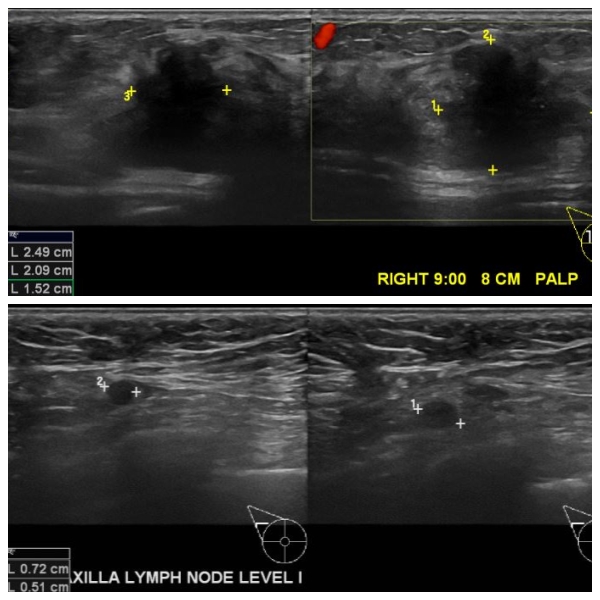

우측 만져지는 멍우리로 내원하신 60대 여성 분으로 우측 9시 방향 8cm 떨어진 거리의

혹 조직검사 시행하여 우측 침윤성 유관암 진단 되었으며, 우측 겨드랑이 림프절 비대

세침검사 시행하여 전이암으로 진단 되었습니다.